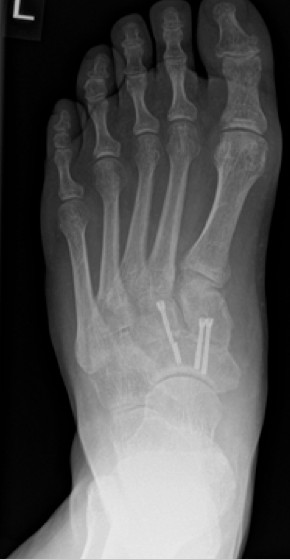

Die Stabilisierung erfolgte nunmehr mittels Platte und einer externen Zugschraube. Es wurde wiederum Knochenersatzmaterial angelagert.

4.- 06/2017 nach Rearthrodese